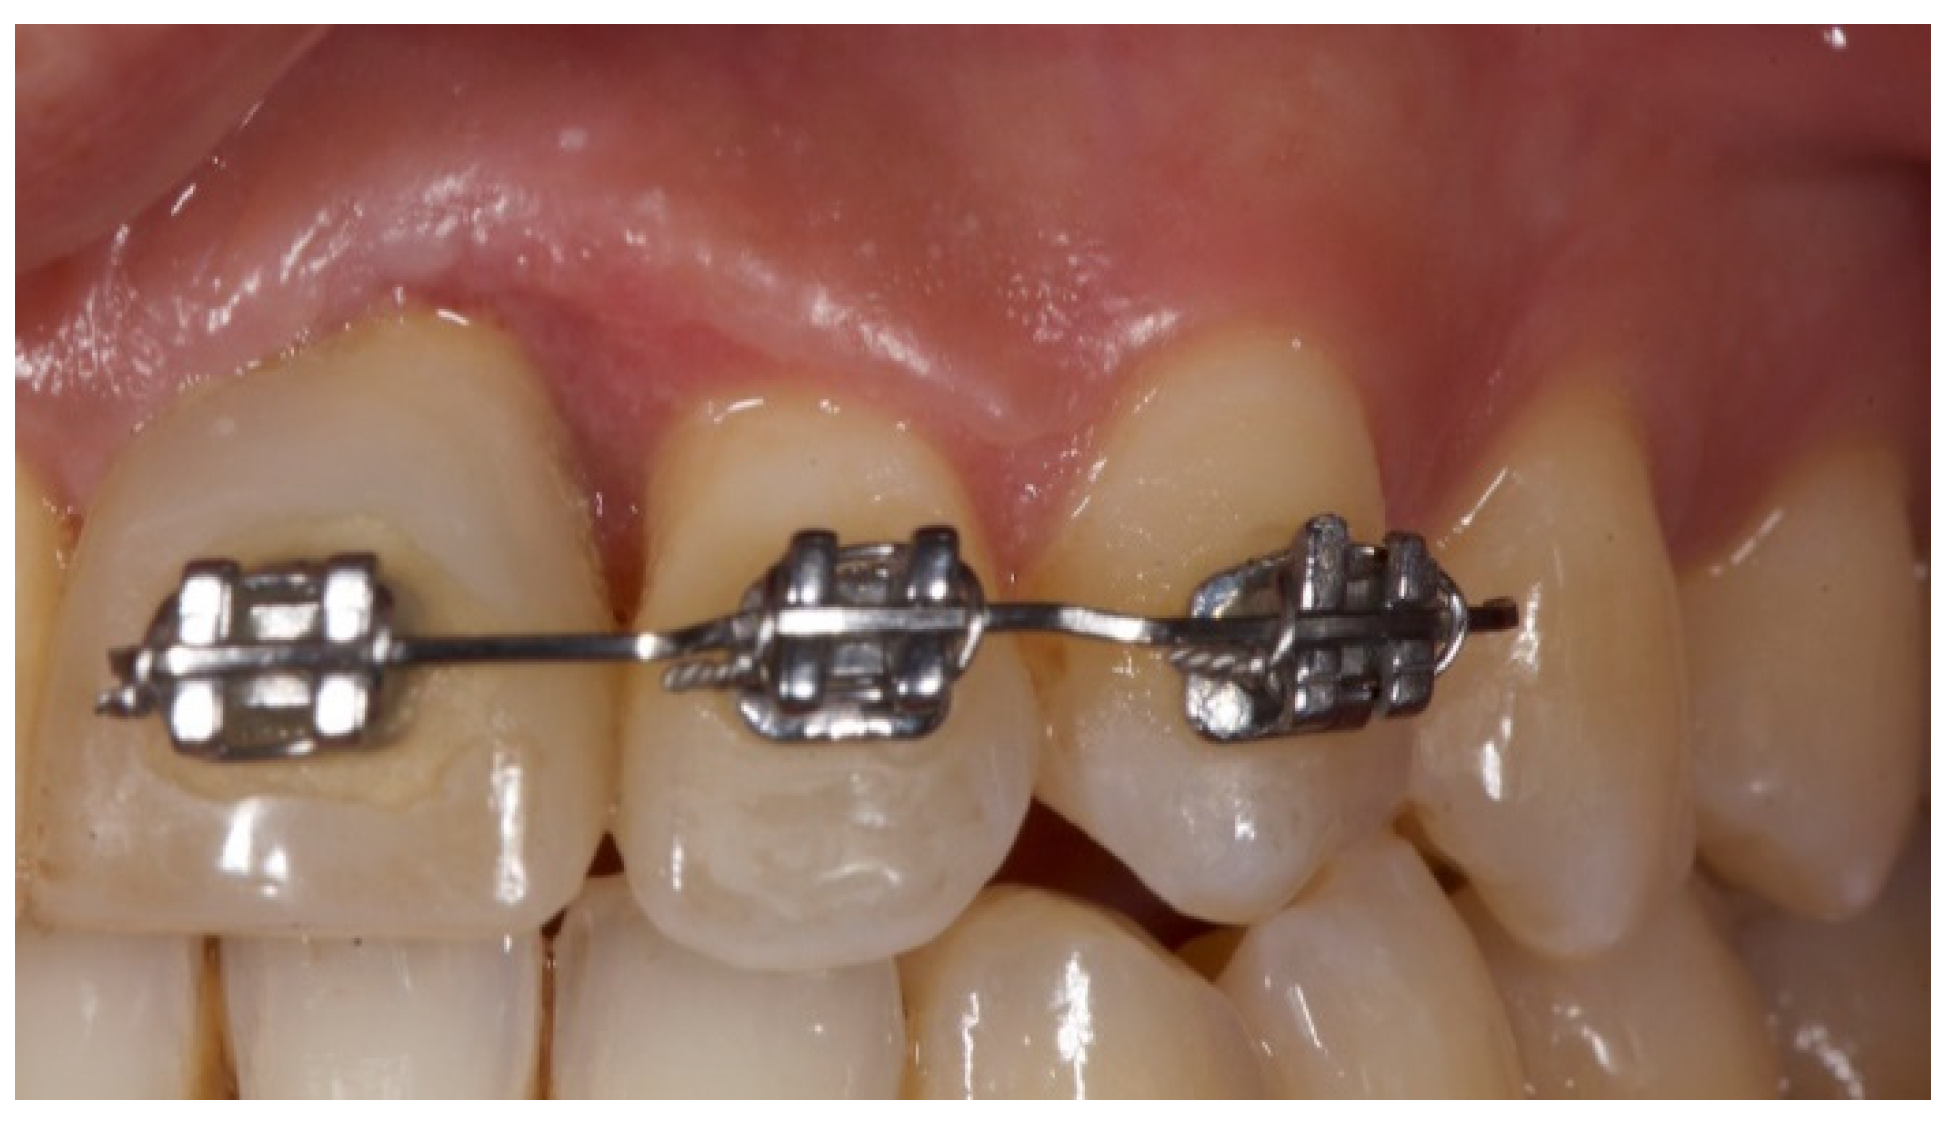

Tissue Recession around a Dental Implant in Anterior Maxilla: How to Manage Soft Tissue When Things Go Wrong?

2. Case Presentation